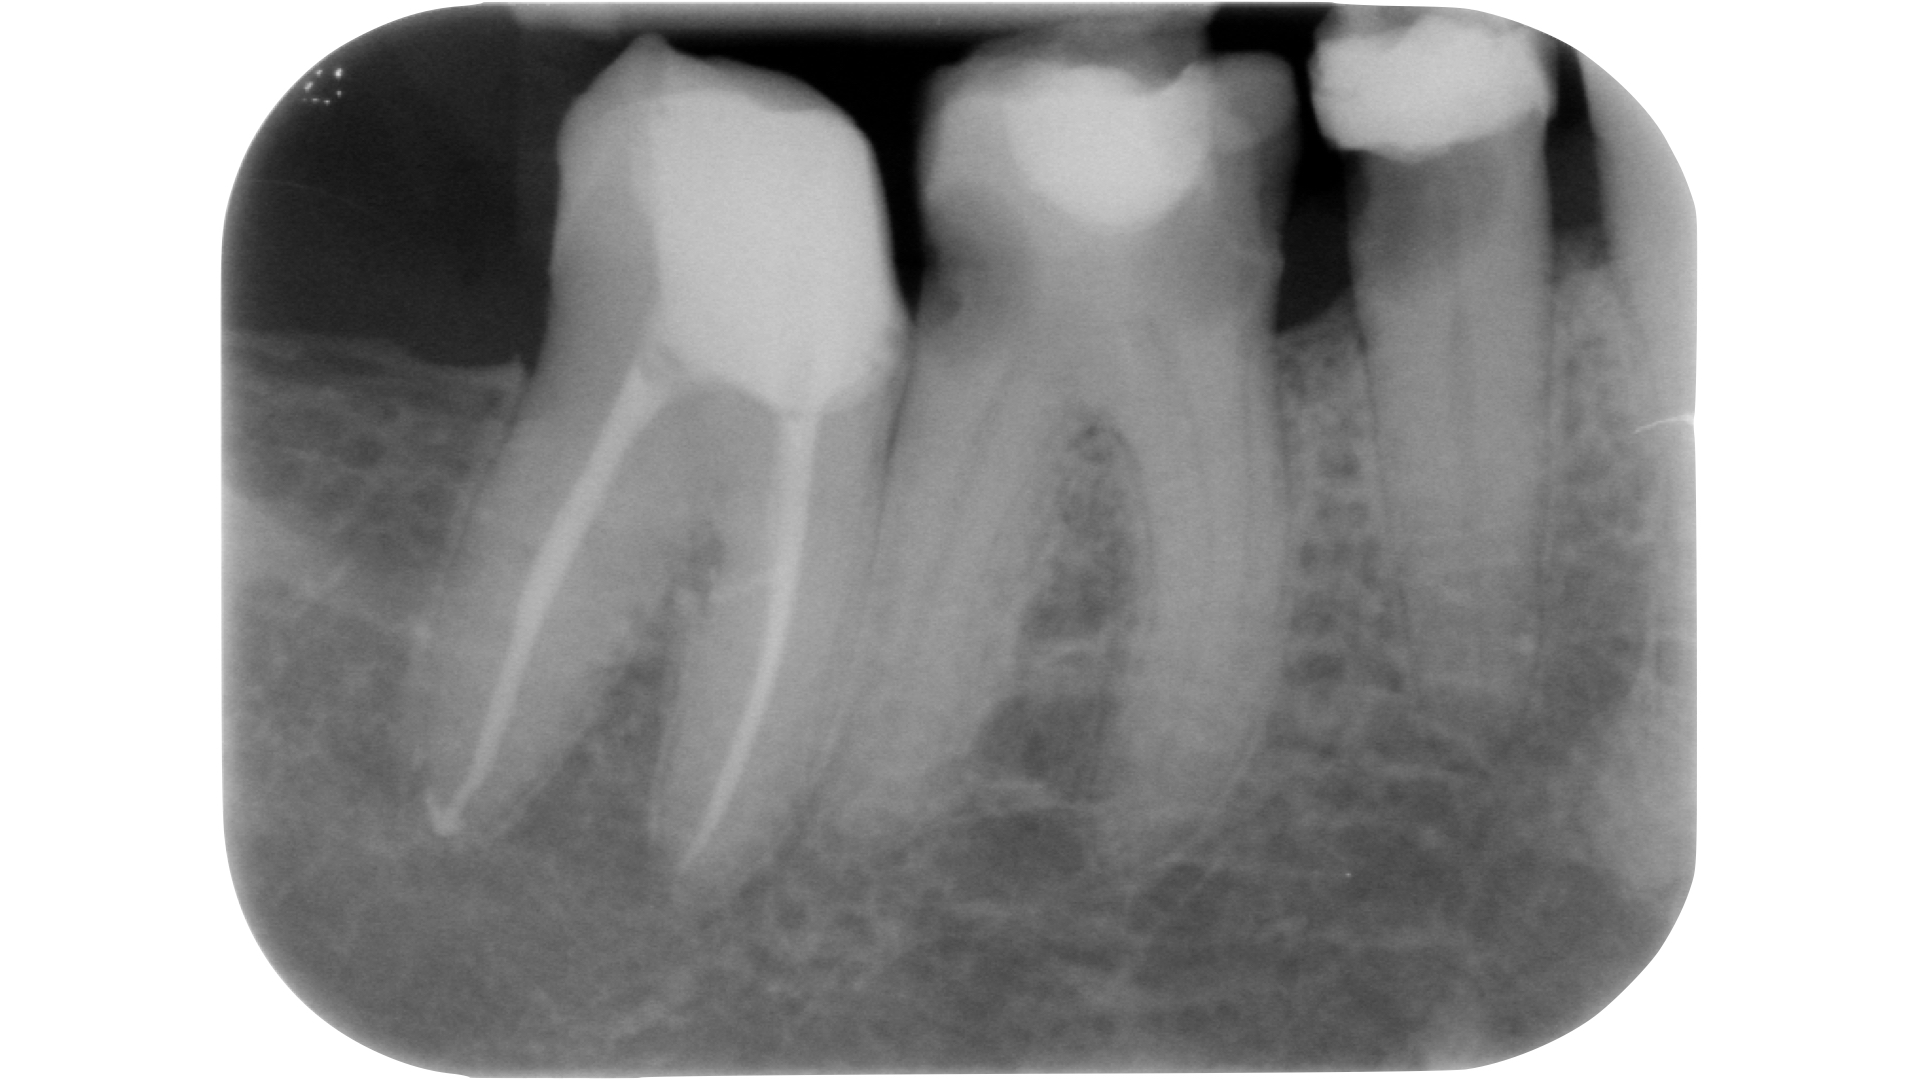

Devono essere valutate con molta attenzione la posizione dell’elemento in arcata e la sua inclinazione (Figure 6-7), l’entità e la posizione del processo carioso se presente, gli eventuali restauri posizionati sul dente e i rapporti con il parodonto: tutte queste considerazioni permetteranno al clinico di capire innanzitutto la mantenibilità e la possibilità di isolare mediante diga di gomma il dente. L’interpretazione degli esami radiografici consentirà inoltre di valutare alcuni parametri preoperatori di notevole importanza:

- qualità dei restauri posizionati sull’elemento dentale ed eventuali infiltrazioni secondarie;

- presenza di radiotrasparenze periradicolari o periapicali;

- difetti ossei di origine parodontale;

- aspetto della camera pulpare e del sistema canalare;

- anatomia radicolare e canalare;

- presenza di pregresse terapie canalari e valutazione della qualità delle stesse;

- presenza o sospetto di riassorbimenti interni o esterni;

- presenza o sospetto di perforazioni e fratture.

Un’attenta analisi di questi dati clinici e radiografici consentirà al clinico di ridurre notevolmente il rischio di errori grossolani in questa delicata fase del trattamento.